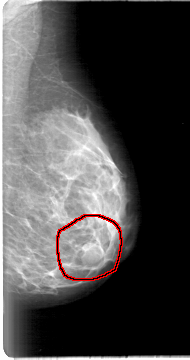

D_4000_1.LEFT_MLO

LEFT_MLO LINES 5386 PIXELS_PER_LINE 2836 BITS_PER_PIXEL 12 RESOLUTION 43.5 OVERLAY

FILE: D_4000_1.LEFT_MLO.OVERLAY

TOTAL_ABNORMALITIES 1

ABNORMALITY 1

LESION_TYPE MASS SHAPE LOBULATED MARGINS CIRCUMSCRIBED

ASSESSMENT 0

SUBTLETY 4

PATHOLOGY BENIGN

TOTAL_OUTLINES 1

BOUNDARY